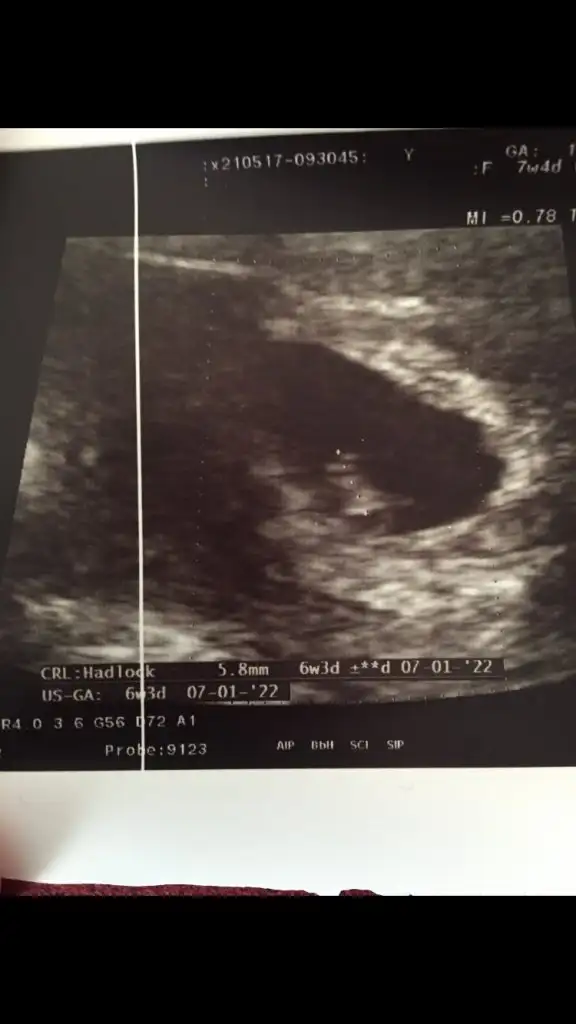

Masallah kuzucuga annesi büyümüş senin ultrason bakinca erkek bebek hissettim cnm

Sağlıkla gelsin bebiş![]()

Ya kızlar canimsiniz siz.duygu patlaması yaşadım mesajlarınıza.Allah sizden bin kere razı olsun.kocaman Amiiin Güzel yurekli kardeşlerim Rabbim hepimize yaşatsın bu mutluluğu.Canımmm bak ümit vermek istemem ama nub tan anladığım kadarıyla bu bebiş erkek yaaaAllahımmm ezanlar okunuyor Rabbim sen yanıltma ne olursun